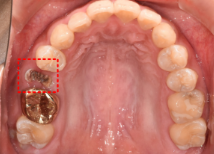

왼쪽 사진에 보시면 빨간색 네모 박스 보이시나요? 이 부분의 치아가 상실되어 임플란트가 필요한 상황이었습니다.

바로 옆에 있는 골드크라운 치아도 교체가 필요한 상황이라.. 임플란트와 골드크라운 교체를 함께 진행하기로 결정하셨는데요.

우측 엑스레이 보시면, 치아 뿌리가 남아있는 상황으로 '치아 뿌리 발치'가 먼저 필요한 상황이었습니다. 방치하게 되면, 통증이 더 심해질 수 있기에 빠르게 발치를 먼저 진행하셨습니다.